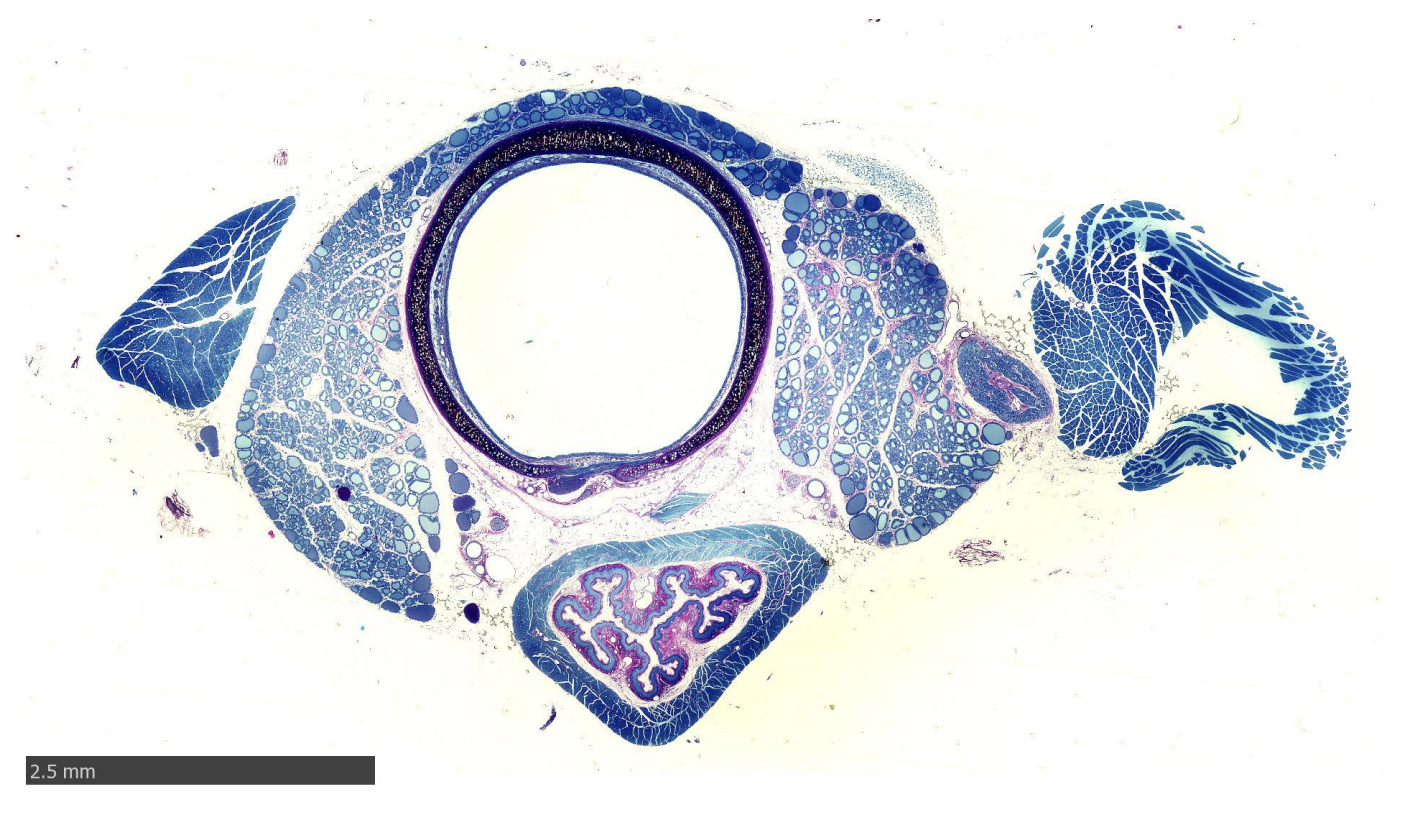

Oesophagus and Trachea of rat

Stained with Azure blue and Basic Fuchsin

Identify:

Nerve trunk

Collagen

3 types of epithelia